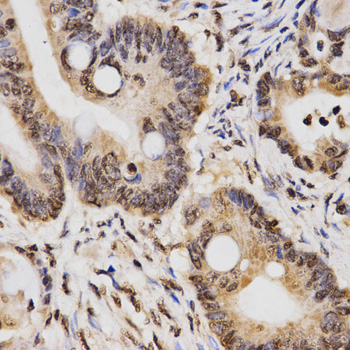

Immunohistochemistry of paraffin-embedded human rectal cancer tissue using H3K14me2 antibody at dilution of 1:200 (x400 lens)